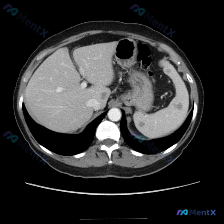

整理了一份最近看到的腹部CT病例资料,重点在于脾脏的异常表现,结合分析报告说说思路。 先看影像基础情况 这是一份横断面腹部增强CT(软组织窗)的描述: - 脾脏:实质内可见片状低密度区,边界相对模糊,位置在脾门附近及脾实质中部; - 肝脏、胃、血管等:其余腹部实质脏器、腹腔脂肪间隙、脊柱肌肉等未见明...

今天整理了一个很有代表性的腹部CT偶然发现病灶的病例,主要是想和大家分享一下这类「脾内孤立低密度灶」的分析思路。 先看影像与基本情况 这是一份上腹部CT横断面软组织窗图像的客观描述: - 肝脏:形态、密度大致正常,无明显大占位,无腹水。 - 脾脏:大小形态基本正常,脾实质内可见一个类圆形局灶性低密度...

最近看到一份很有警示意义的腹部增强CT资料,整理一下思路和大家分享。 先看影像核心表现 这份是上腹部增强CT横断面软组织窗,主要异常集中在肝脏和脾脏: 1. 脾脏:体积稍大,脾实质内可见多发类圆形低密度结节灶,边界清晰,部分病灶边缘可见强化,呈「靶征」或「环形强化」改变。 2. 肝脏:肝实质内也可见...